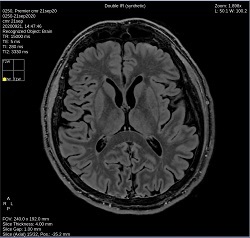

- By default, a 6-viewport display is launched with 6 unique MAGiC images.